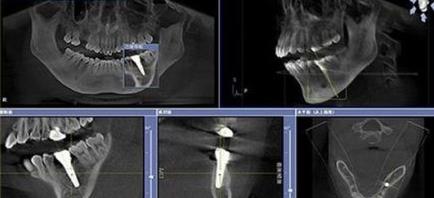

而且醫生提示,每個(ge) 人的牙齒具體(ti) 情況是不同的,比如說是否需要拔牙,是否需要做植骨手術,是否需要先做牙周治療等,都是需要根據每個(ge) 人的情況來確定的,如果需要,自然也會(hui) 增加相應的費用。而且牙齒缺失修複不止種植牙一種,大家需要檢查牙齒情況選擇適合自己的方式才好。